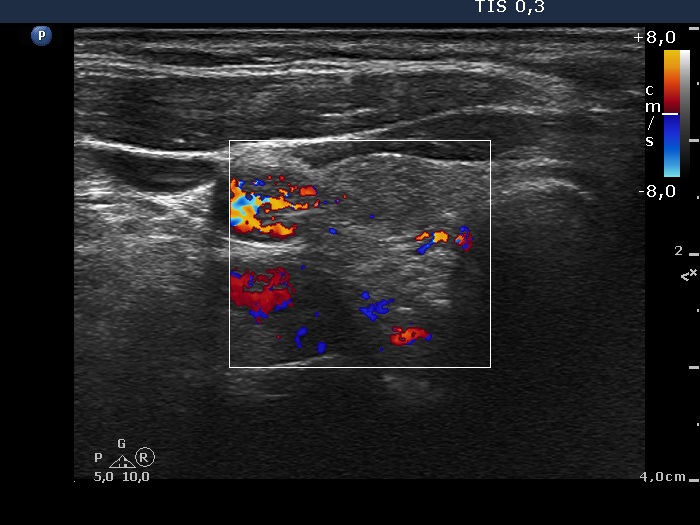

Ultrasonography. The thyroid was echonormal. There was a minimally-moderately hypoechogenic nodule in the right while a cystic nodule in the left lobe. There were numerous hyperechogenic figures both in the cystic and in the lower solid part of the lesion. The lesion presented no vascularization.